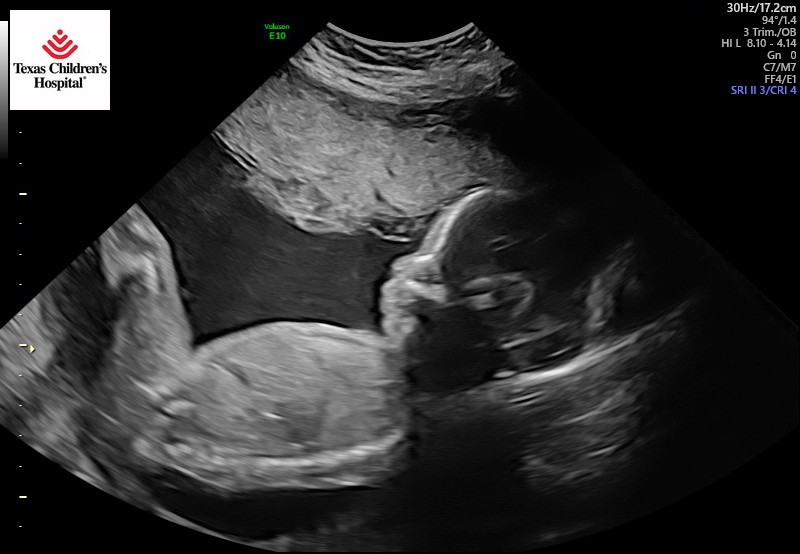

I don’t like it when my Mama Rosa cries. She cried the day (January 16, 2023…MLK Day) we had our Anatomy Ultrasound when I was only 20 gestational weeks old. First, the male ultrasound technician pushed down very hard when doing the exam and it hurt Mama. A few hours later, Mama received a telephone call from the office of her OB/GYN Dr. Megan Karjola. She wanted to see mama that evening at 5:00pm. Mama new something was wrong. While my daddy stayed home with my three brothers (they can never be left alone), my Mama and Grandma went to the doctors office. The ultrasound technician detected clues I may have Spina Bifida. Mom cried. The technician thinks I have a “lemon head.” That is not a nice thing to say. Grandma said so! To be sure, Dr. Karjola arranged for Mama and Me to have a special 3D ultrasound appointment at The Ogden Women’s Center. One week later, on January 24, around noon, it was confirmed. I have a birth defect called Myelomeningocele (pronounced my-low-ma-nin-jo-seal)—Spina Bifida, the severe type. She cried some more. So did daddy.